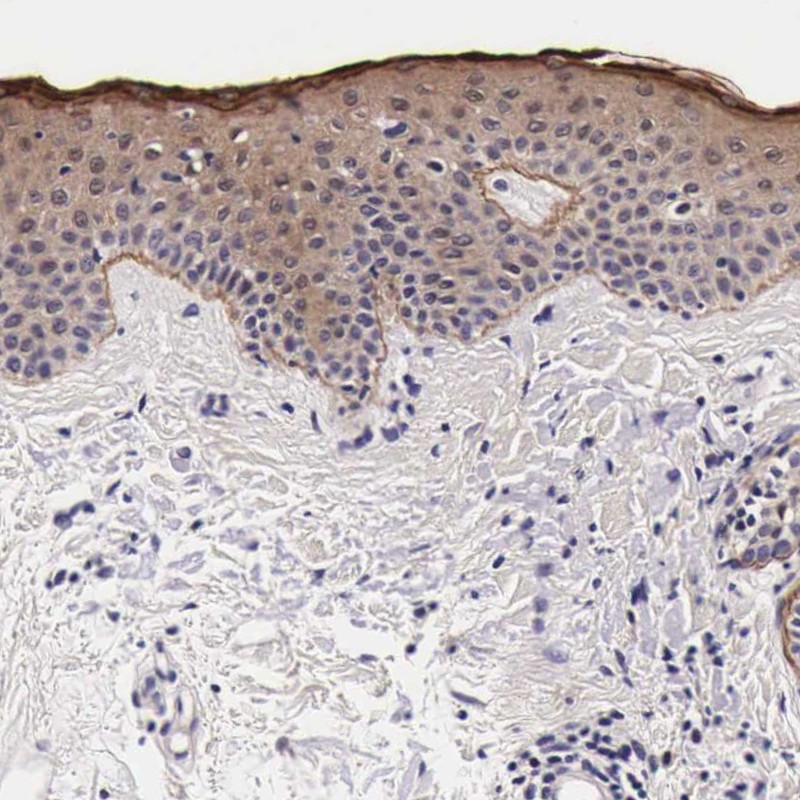

Immunohistochemical staining of human skin shows moderate cytoplasmic positivity mainly in keratinocytes.